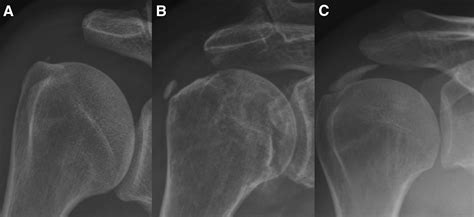

The condition generally progresses through several distinct phases:

• Pre-calcific stage: The cells in the tendon undergo changes that predispose the tissue to calcium deposit formation. Patients typically experience no symptoms during this phase.

• Calcific stage: This is when the calcium crystals actually form. The deposits can grow, causing mild to moderate discomfort as they take up space in the tendon.

• Resorptive stage: This is the most painful phase. The body recognizes the calcium deposits as foreign objects and initiates an inflammatory response to break them down and resorb them. This inflammation causes intense pressure and severe pain.

• Post-calcific stage: The calcium deposits have been successfully resorbed, and the tendon begins to remodel and heal itself. Pain gradually subsides.